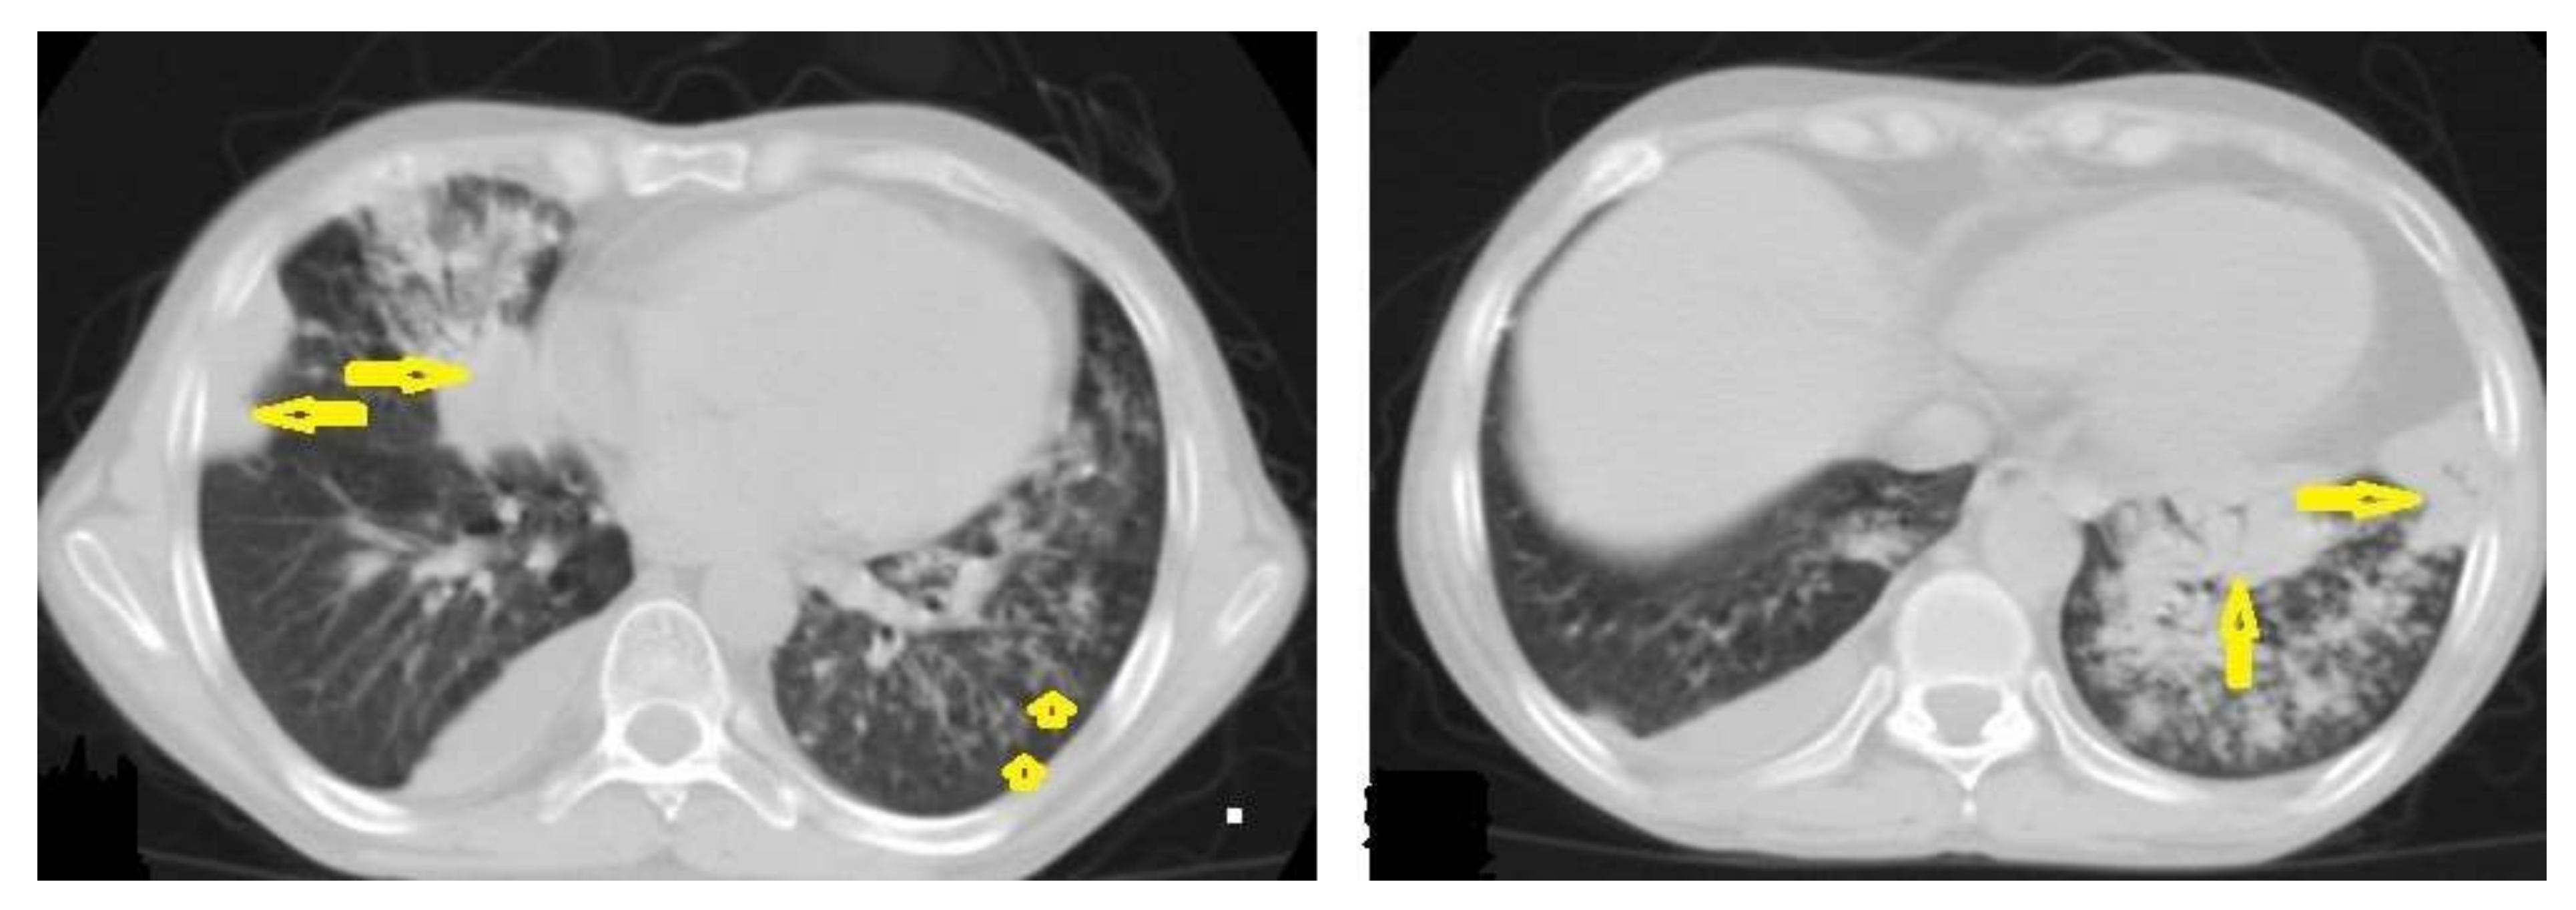

Figure 17. A tuberculous abscess in the cerebellum of a 13-year-old female (same patient as Figure 16). Selected images of brain MRI (a) T1-weighted image (WI), (b) FLAIR-WIs, (c) T1-WI with contrast, and (d) diffusion-weighted (DW) image. The images show a well-defined lesion in the cerebellum with low signal intensity content and a high signal intensity capsule on T1WI and FLAIR (b), marginal enhancement on T1WI with contrast administration (c), and restricted diffusion on DWI (d).

• Tuberculous abscesses (Figure 15, Figure 16 and Figure 17) are an infrequent pattern of brain TB, which are present in immunocompromised and elderly patients. They occur either due to the progression of cerebritis or the liquefaction of tuberculoma. On a brain CT, it occurs as a low density area with ring enhancement after contrast administration and the surrounding low density area of edema. On a brain MRI, it appears as a circular or elliptical area of low intensity with ring enhancement after contrast administration and surrounding low intensity area of edema on T1WIs and high intensity area with a high intensity surrounding edema. Tuberculous abscess is a difficult differential diagnosis of a pyogenic abscess, pilocystic astrocytoma, and other cystic lesions. MR spectroscopy may help in differentiating tuberculous from a pyogenic abscess [27,33].